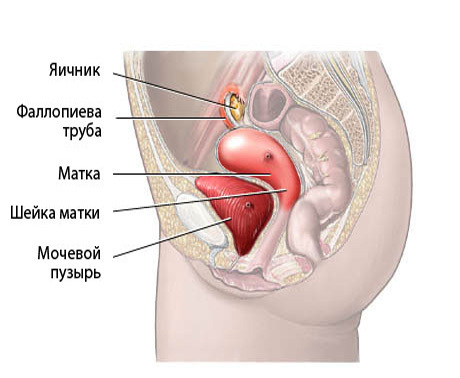

Анатомия женского организма: строение и функции матки

Раздел: Фотопуть к знанию